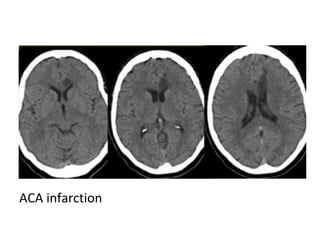

ACA infarction